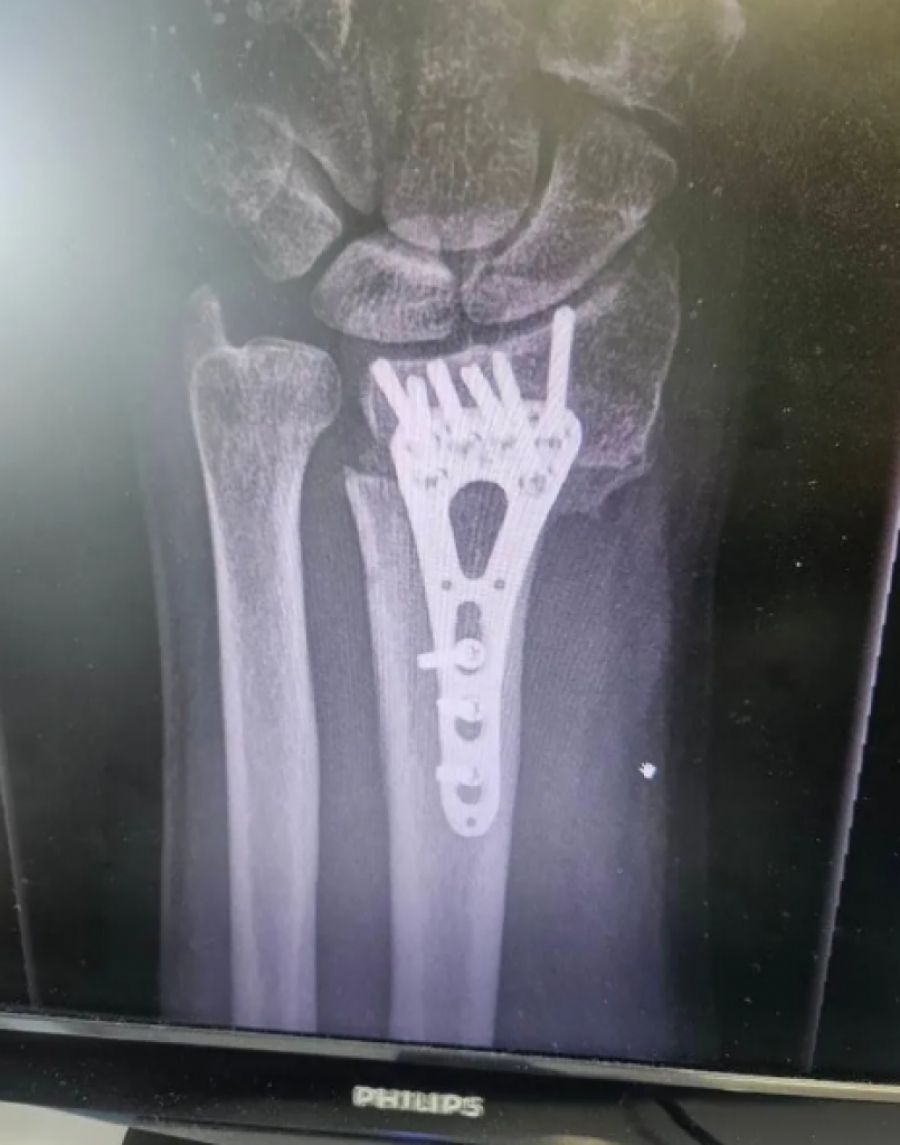

Voditelj Aleksandar Stanković podelio je fotografiju jezive povrede zbog koje je hitno operisan. Naime, Stanković je objavio uznemirujuću fotografiju iskrivljene ruke, zbog koje je morao da se podvrgne operaciji.

Strašna povreda dogodila se pre tri meseca, a on je sada pokazao kako je izgledao proces oporavka.

- Ovako je to izgledalo prije 3 meseca, a danas je sve u redu. Slomio sam ruku (prva fotka) i operisali su me u Opštoj bolnici Sisak na čelu s doktorom Abelom Balaškom. Ruka je zacelila i hvala im što su svoj posao odradili profesionalno i s ljubavlju! - napisao je.